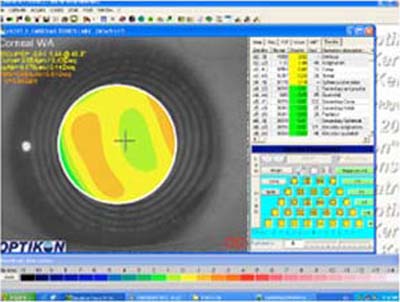

1 - Queratografía

2 - Topografía de alto poder

3 - Topografía de bajo poder

Con la difusión de la cirugía refractiva a finales de los años 70 y comienzos de los 80, fué necesario mejorar la metodología clínica existente para medir la superficie anterior de la córnea. Basados en el Queratómetro, se desarrollaron los Fotoqueratoscopios para poder capturar la imágen de los anillos del Disco de Placido reflejados sobre la córnea,pudiendo así, apreciar en forma cualitativa, distorsiones inherentes a una forma de córnea individual; ( foto N° 1)

Debido a que clínicamente era necesario poder cuantificar las distorsiones percibidas, se desarrollaron los Videoqueratoscopios que utilizan métodos computarizados para capturar la información de la imágen queratoscópica y reconstruir a partir de ella la superficie anterior de la córnea, graficandola de una manera util y facil de entender para el médico oftalmólogo. Esta técnología es conocida como Topografía Corneal.

Con esta metodología, los poderes altos de la superficie corneal son representados en colores cálidos como el amarillo, naranja y rojo (Foto 2) mientras que las áreas de bajo poder se las representa en colores más frios como el verde y el azul. ( Foto 3), facilitandose así visualización de los efectos de la cirugía refractiva y la comprensión de sus resultados ( Foto 4 y 5)